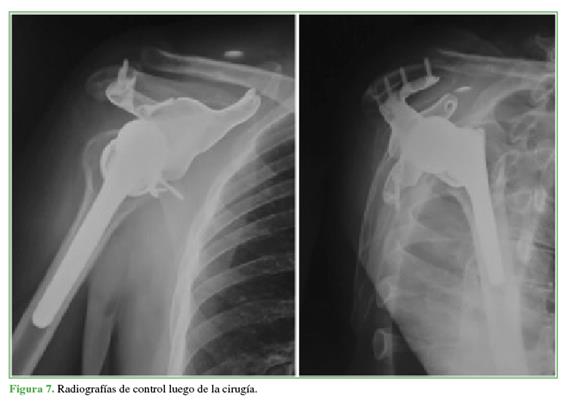

Se utilizaron las guías de corte para resecar la masa tumoral y se colocó la prótesis impresa en 3D con parte de apoyo en el acromion para una mayor fijación y estabilidad del componente, a fin de contrarrestar las cargas axiales y mejorar el funcionamiento de la prótesis invertida asociada. Se resecó la masa tumoral con márgenes macroscópicamente libres, se reparó el deltoides con suturas reforzadas y se constató la estabilidad de la prótesis (Figura 6). Se tomaron radiografías de control (Figura 7).